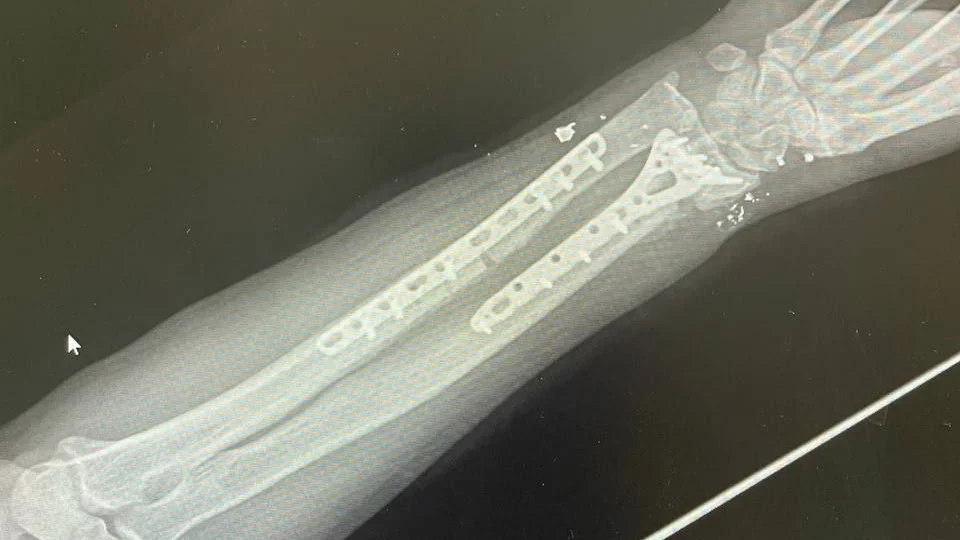

Рентген руки Александра Прозорова с пластинами для сращивания сломанных костей

Довольствия не хватает, так что инвалид второй группы вынужден работать сварщиком и подвизаться во Владивостоке на ремонтах. Не скрывает — в квартире на 24-м этаже новостройки на ул. Полковника Фесюна, 20 (микрорайон, построенный в основном для военнослужащих и молодых семей), работал вечерами, иногда ночью. Сосед снизу его просил не шуметь, а потом (в ту ночь Прозоров штукатурил стены, таскал лестницу, ведро со штукатуркой) не выдержал, пришел с палкой. Рука «героя» после огнестрельного ранения уже была на металлических пластинах, так что для нового перелома много усилий не потребовалось. Что, конечно, обидчика не оправдывает, но и для уголовного дела, которого так добивается Александр, повода не дает. Так и полиция считает: «умышленное причинение легкого вреда здоровью», административка.

«Стук чем-то тяжелым в дверь, я подошел, открыл и сразу без слов получил бруском большим в голову. Я упал, и сосед начал меня забивать по всему телу палкой, вся голова в шишках. Я закрывал голову руками. И, естественно, [он] сломал мне правую руку вместе с пластинами. Потом я потерял сознание. Когда пришел в себя, вызвал сотрудников полиции и скорую помощь, так как сам не мог даже встать. Меня доставили в тысячекоечную больницу, сделали рентген. Локтевая кость сломана вместе с титановой пластиной… Сейчас у меня впереди серьезная операция, так как нужна пересадка костей с бедра или заказывать искусственную кость».